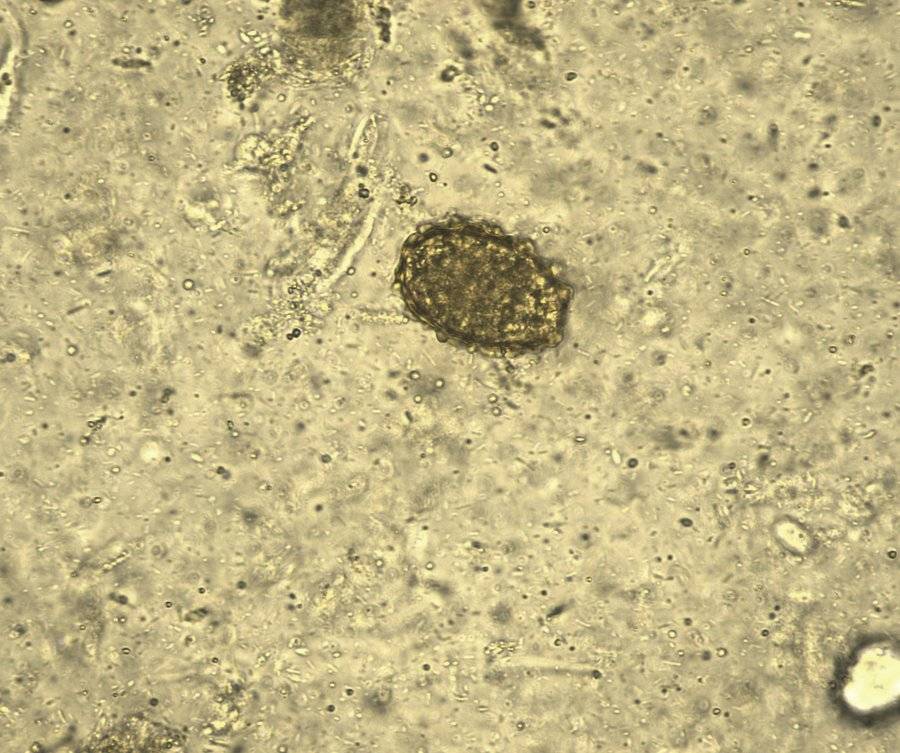

25号 S25 腰鼓藏“塞”—鞭虫卵

鞭虫卵大小约(50-54)x(22-23)μm,黄褐色,腰鼓形或橄榄状,卵壳较厚,两端各有一个透明塞,刚排出时内含未分裂卵细胞,预防鞭虫感染的核心是切断“粪-口传播”,关键做好卫生与环境管理。